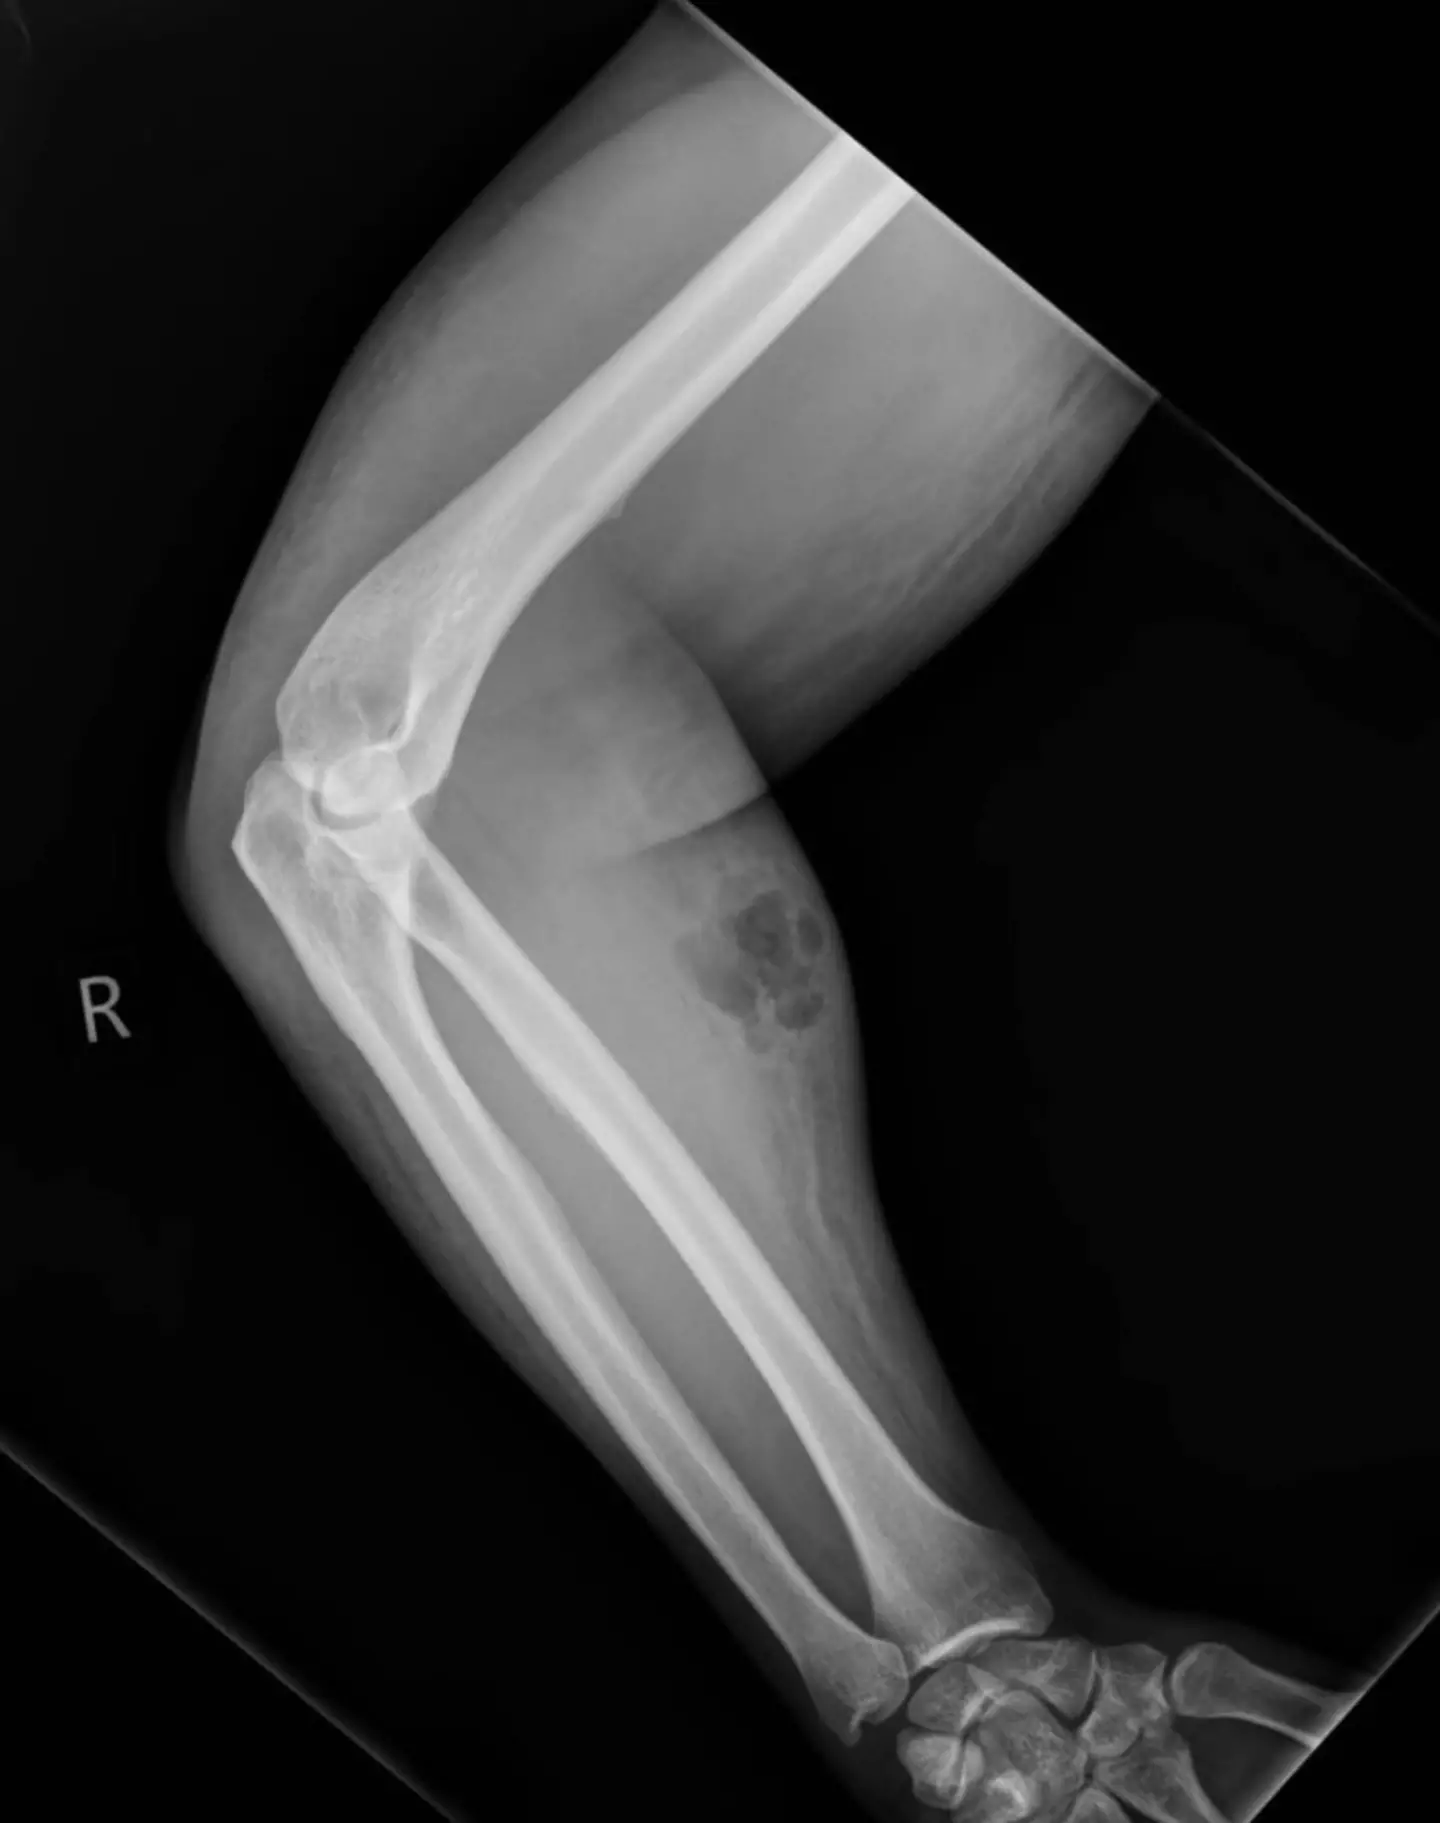

He proceeded to undergo an X-ray which found that he had subcutaneous emphysema and a collection of semen in his muscle. The man needed urgent antibacterial treatment as a result.

An X-ray showed the build up of semen under the man’s skin (Irish Medical Journal)